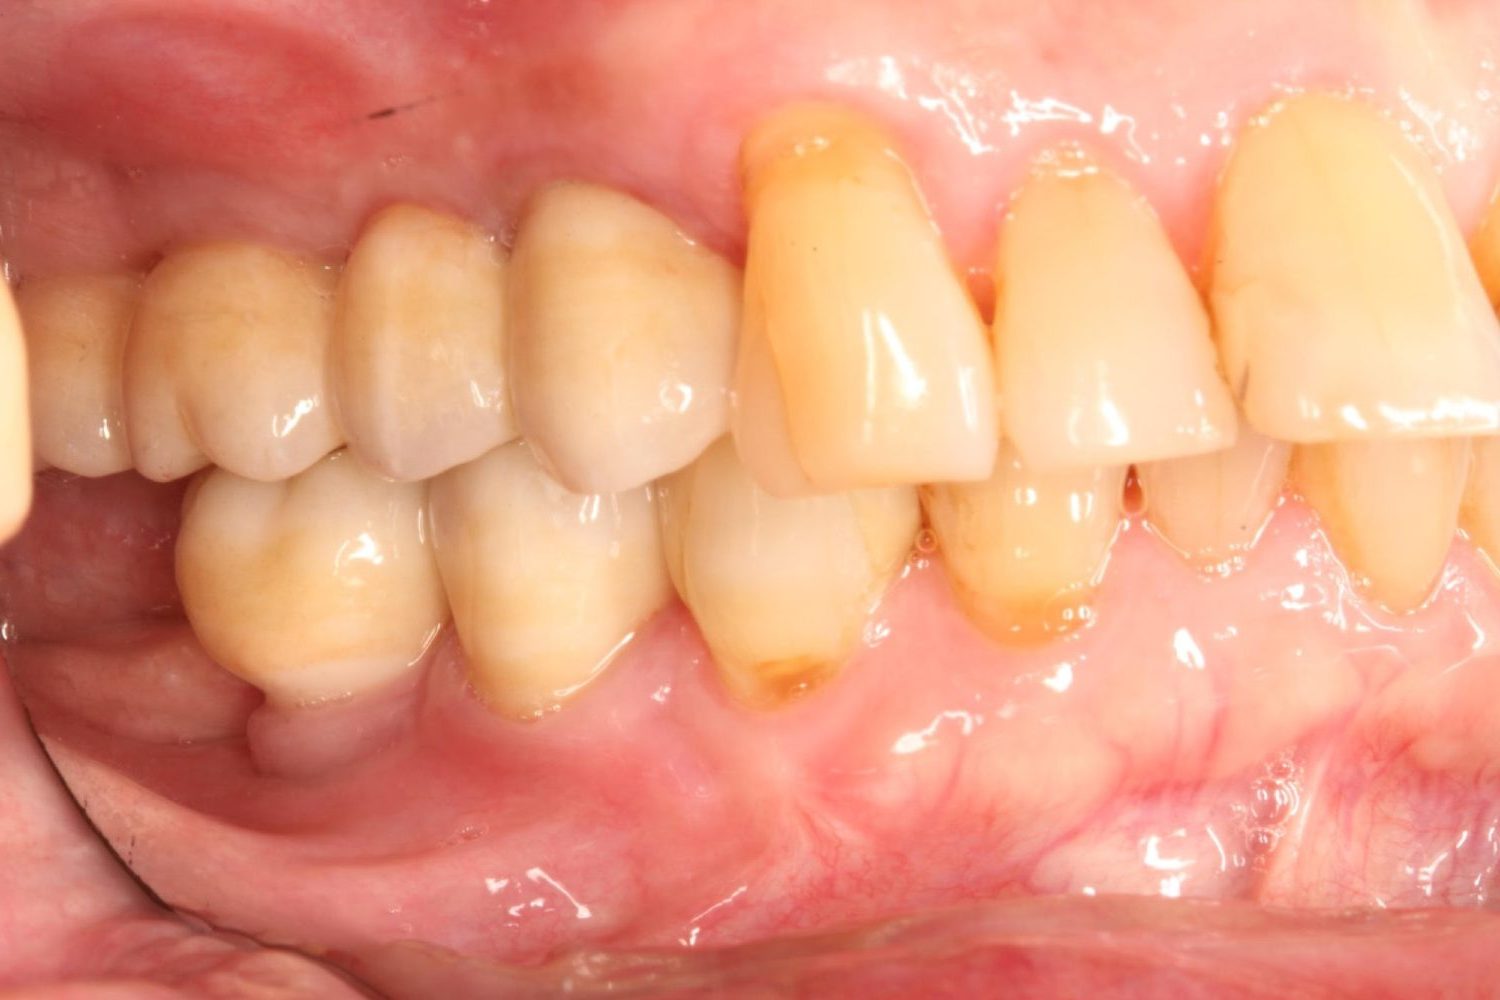

インプラント治療の症例紹介④

Before

After

主訴

義歯による疼痛

治療内容

下顎舌側に骨隆起があり義歯困難な状態。保存不可能な歯の抜歯を行い、インプラントを埋入し咬合再構成を行った。

治療費

2,851,200円(税込)

治療期間

29ヶ月

通院回数

26回

想定されたリスク

※咬合力の強い方なので、予防的にマウスピースの装着が必要。インプラント周囲炎の恐れがありました。

濱 仁隆先生

浜歯科

歯の欠損の対合歯の挺出等を修正し咬合平面を揃え咬合再構成を行った症例。